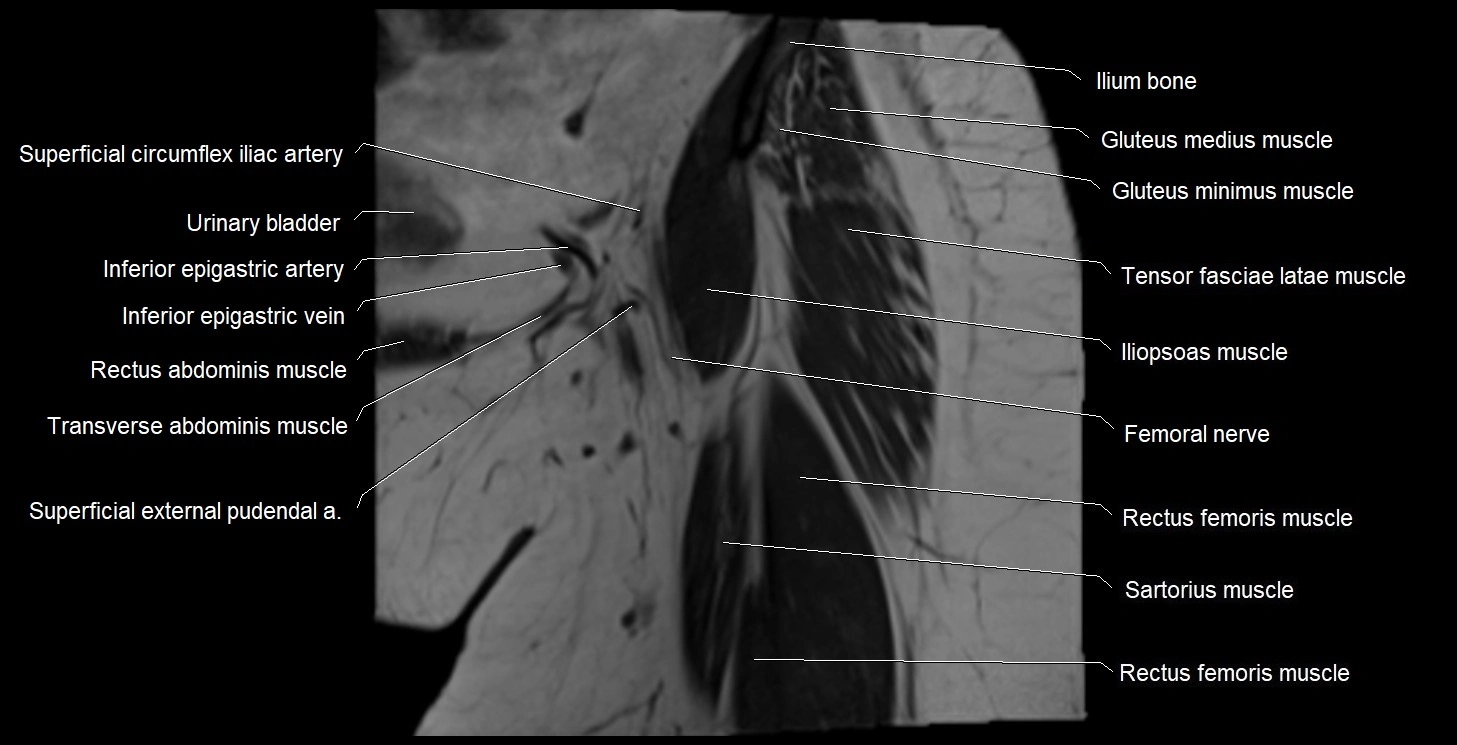

- Femoral nerve

- Iliopsoas muscle

- Iliopsoas tendon

- Inferior epigastric artery

- Inferior epigastric veins

- Rectus femoris muscle

- Sartorius muscle

- Superficial circumflex iliac artery

- Tensor fasciae latae muscle

- Urinary bladder

- Vastus intermedius muscle

- Vastus lateralis muscle